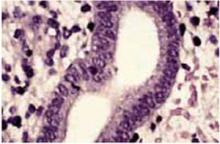

Simple hyperplasia is characterized by benign proliferation of endometrial glands, which are irregular and perhaps dilated, but which lack back-to-back crowding or cellular atypia (FIGURE 1).

FIGURE 1 Simple hyperplasia without atypia

Simple hyperplasia with irregular glands but no back-to-back crowding or cellular atypia (hematoxylin & eosin×100).

High-power magnification of simple hyperplasia without atypia. The nuclei are uniform without cellular atypia (hematoxylin & eosin×400).